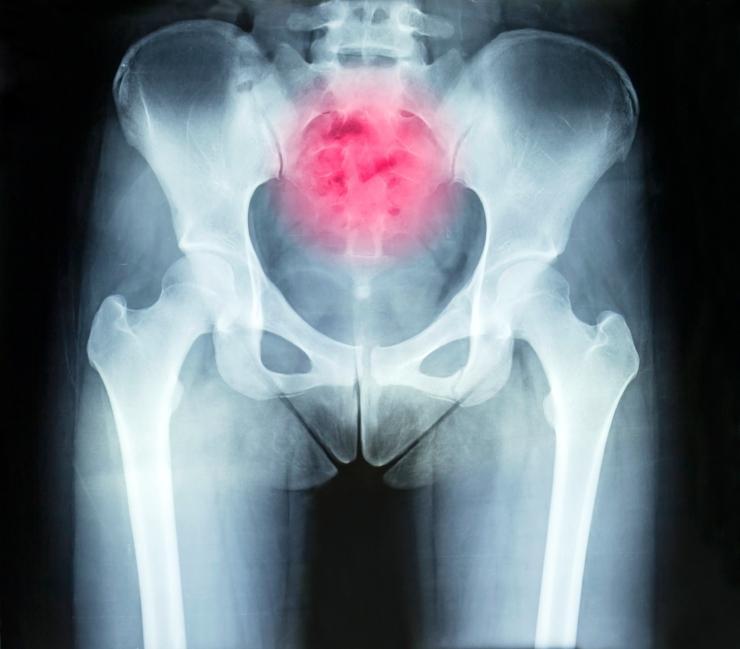

Neste caso, o especialista fará um exame de raio X, um TAC ou uma ressonância magnética, desta forma poderá determinar a origem da sua dor e, assim, tratá-la de forma específica. Também é muito comum que injetem anestesia local na zona para avaliar a diferença com o cóccix relaxado.